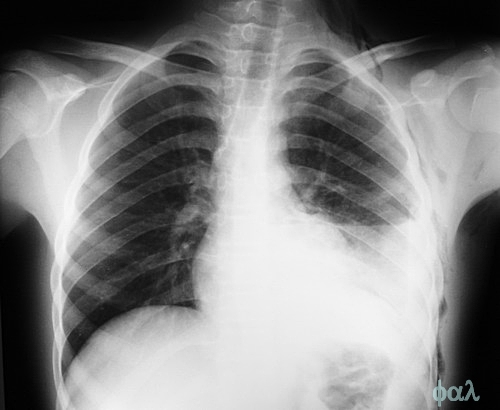

O câncer de pulmão é mais frequente em pessoas com mais de 65 anos de idade, especialmente aquelas que fumaram durante a vida. Como a doença não causa sintomas evidentes na fase inicial, é comum que o diagnóstico ocorra quando a doença já se encontra em estágio avançado.